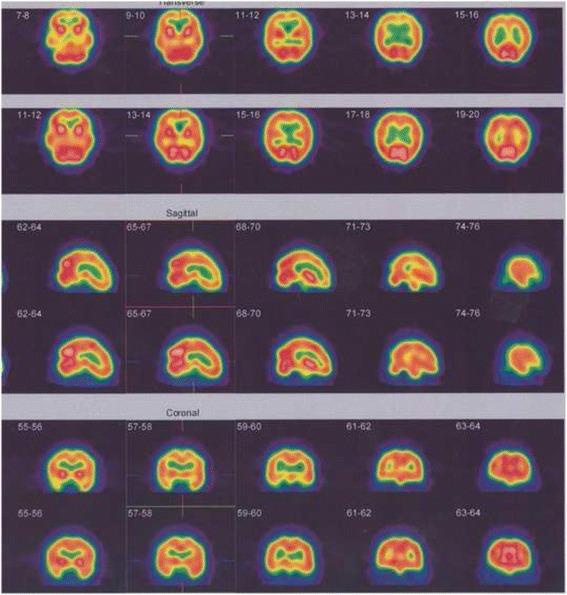

METHODS

We retrospectively reviewed 25 secondary progressive (SP)-MS patients from the hospital database. Neurological disability evaluated by Expanded Disability Status Scale Score (EDSS). Brain perfusion was performed by (99 m) Tc-labeled bicisate (ECD) brain SPECT and the data were compared using statistical parametric mapping (SPM). In total, 16 patients underwent HBOT. Before HBOT and at the end of 20 sessions of oxygen treatment, 99mTc-ECD brain perfusion single photon emission computed tomography (SPECT) was performed again then the results were evaluated and compared. Brain perfusion was performed by (99 m) Tc-labeled bicisate (ECD) brain SPECT and the data were compared using statistical parametric mapping (SPM).

RESULTS

A total of 25 SP-MS patients, 14 females (56 %) and 11 males (44 %) with a mean age of 38.92 ± 11.28 years included in the study. The mean disease duration was 8.70 ± 5.30 years. Of the 25 patients, 2 (8 %) had a normal SPECT and 23 (92 %) had abnormal brain perfusion SPECT studies. The study showed a significant association between severity of perfusion impairment with disease duration and also with EDSS (P <0.05). There was a significant improvement in pre- and post-treatment perfusion scans (P <0.05), but this did not demonstrate a significant improvement in the clinical subjective and objective evaluation of patients (P >0.05).